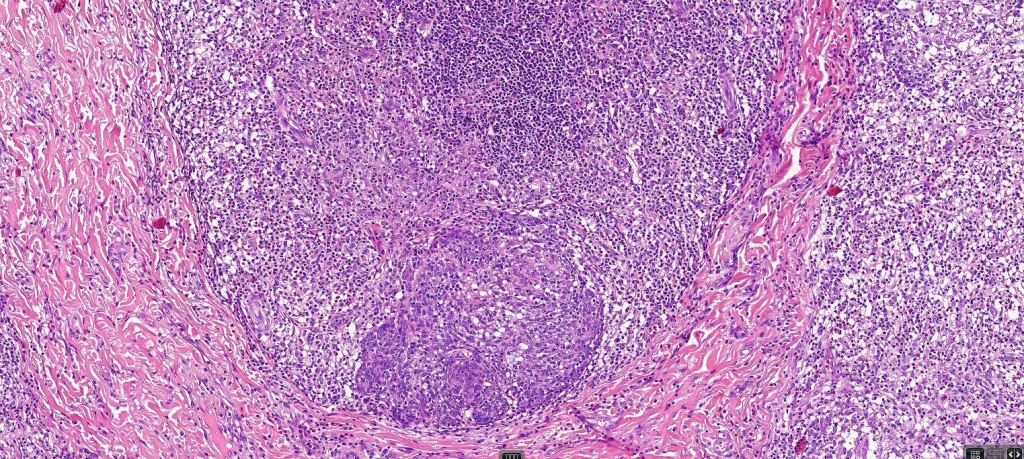

Histological features

•Follicular infiltration by atypical lymphocytes & Sézary cells

•+/- basaloid follicular hyperplasia

•Granulomatous inflammation secondary to follicular destruction